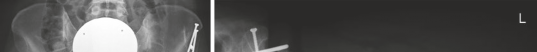

If the patient requires a derotational femoral osteotomy to correct the 36° anteversion, it is performed at this stage. A subtrochanteric osteotomy is executed, the femur is externally rotated to achieve a normalized anteversion of approximately 15°, and rigid fixation is achieved using a pre-contoured locking plate or a blade plate. Following the intra-articular and femoral work, the hip is reduced. The capsule is meticulously closed; a watertight closure is essential to prevent post-operative macro-instability and restore the proprioceptive function of the capsule. Finally, the greater trochanter is reduced and fixed using two or three fully threaded 4.5 mm cortical screws directed medially and slightly proximally toward the lesser trochanter.